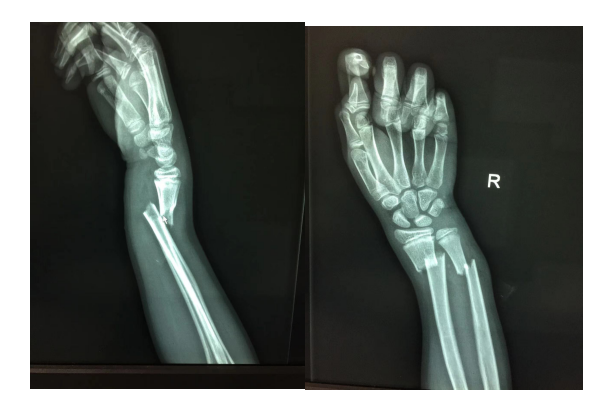

“大夫,大夫,快看看我的孩子,他摔了一下,手一动就疼!”患儿家长焦急而又恐慌的对值班大夫孟祥栋说道。经询问,患儿在家玩耍的时候不小心摔倒了地上,之后就一直说手腕疼,起初大家都没有在意,但是两个小时后,孩子的右手腕越来越疼,并伴有明显肿胀,父母急忙带孩子来到了我院。孟祥栋立刻为患儿安排了拍片检查,结果显示:患儿右尺桡骨远端骨折,并向桡侧背侧移位。

经小儿骨科副主任医师孟祥栋手法复位、夹板外固定,X线光片可见:右尺桡骨远端骨折断端对位对线良好。